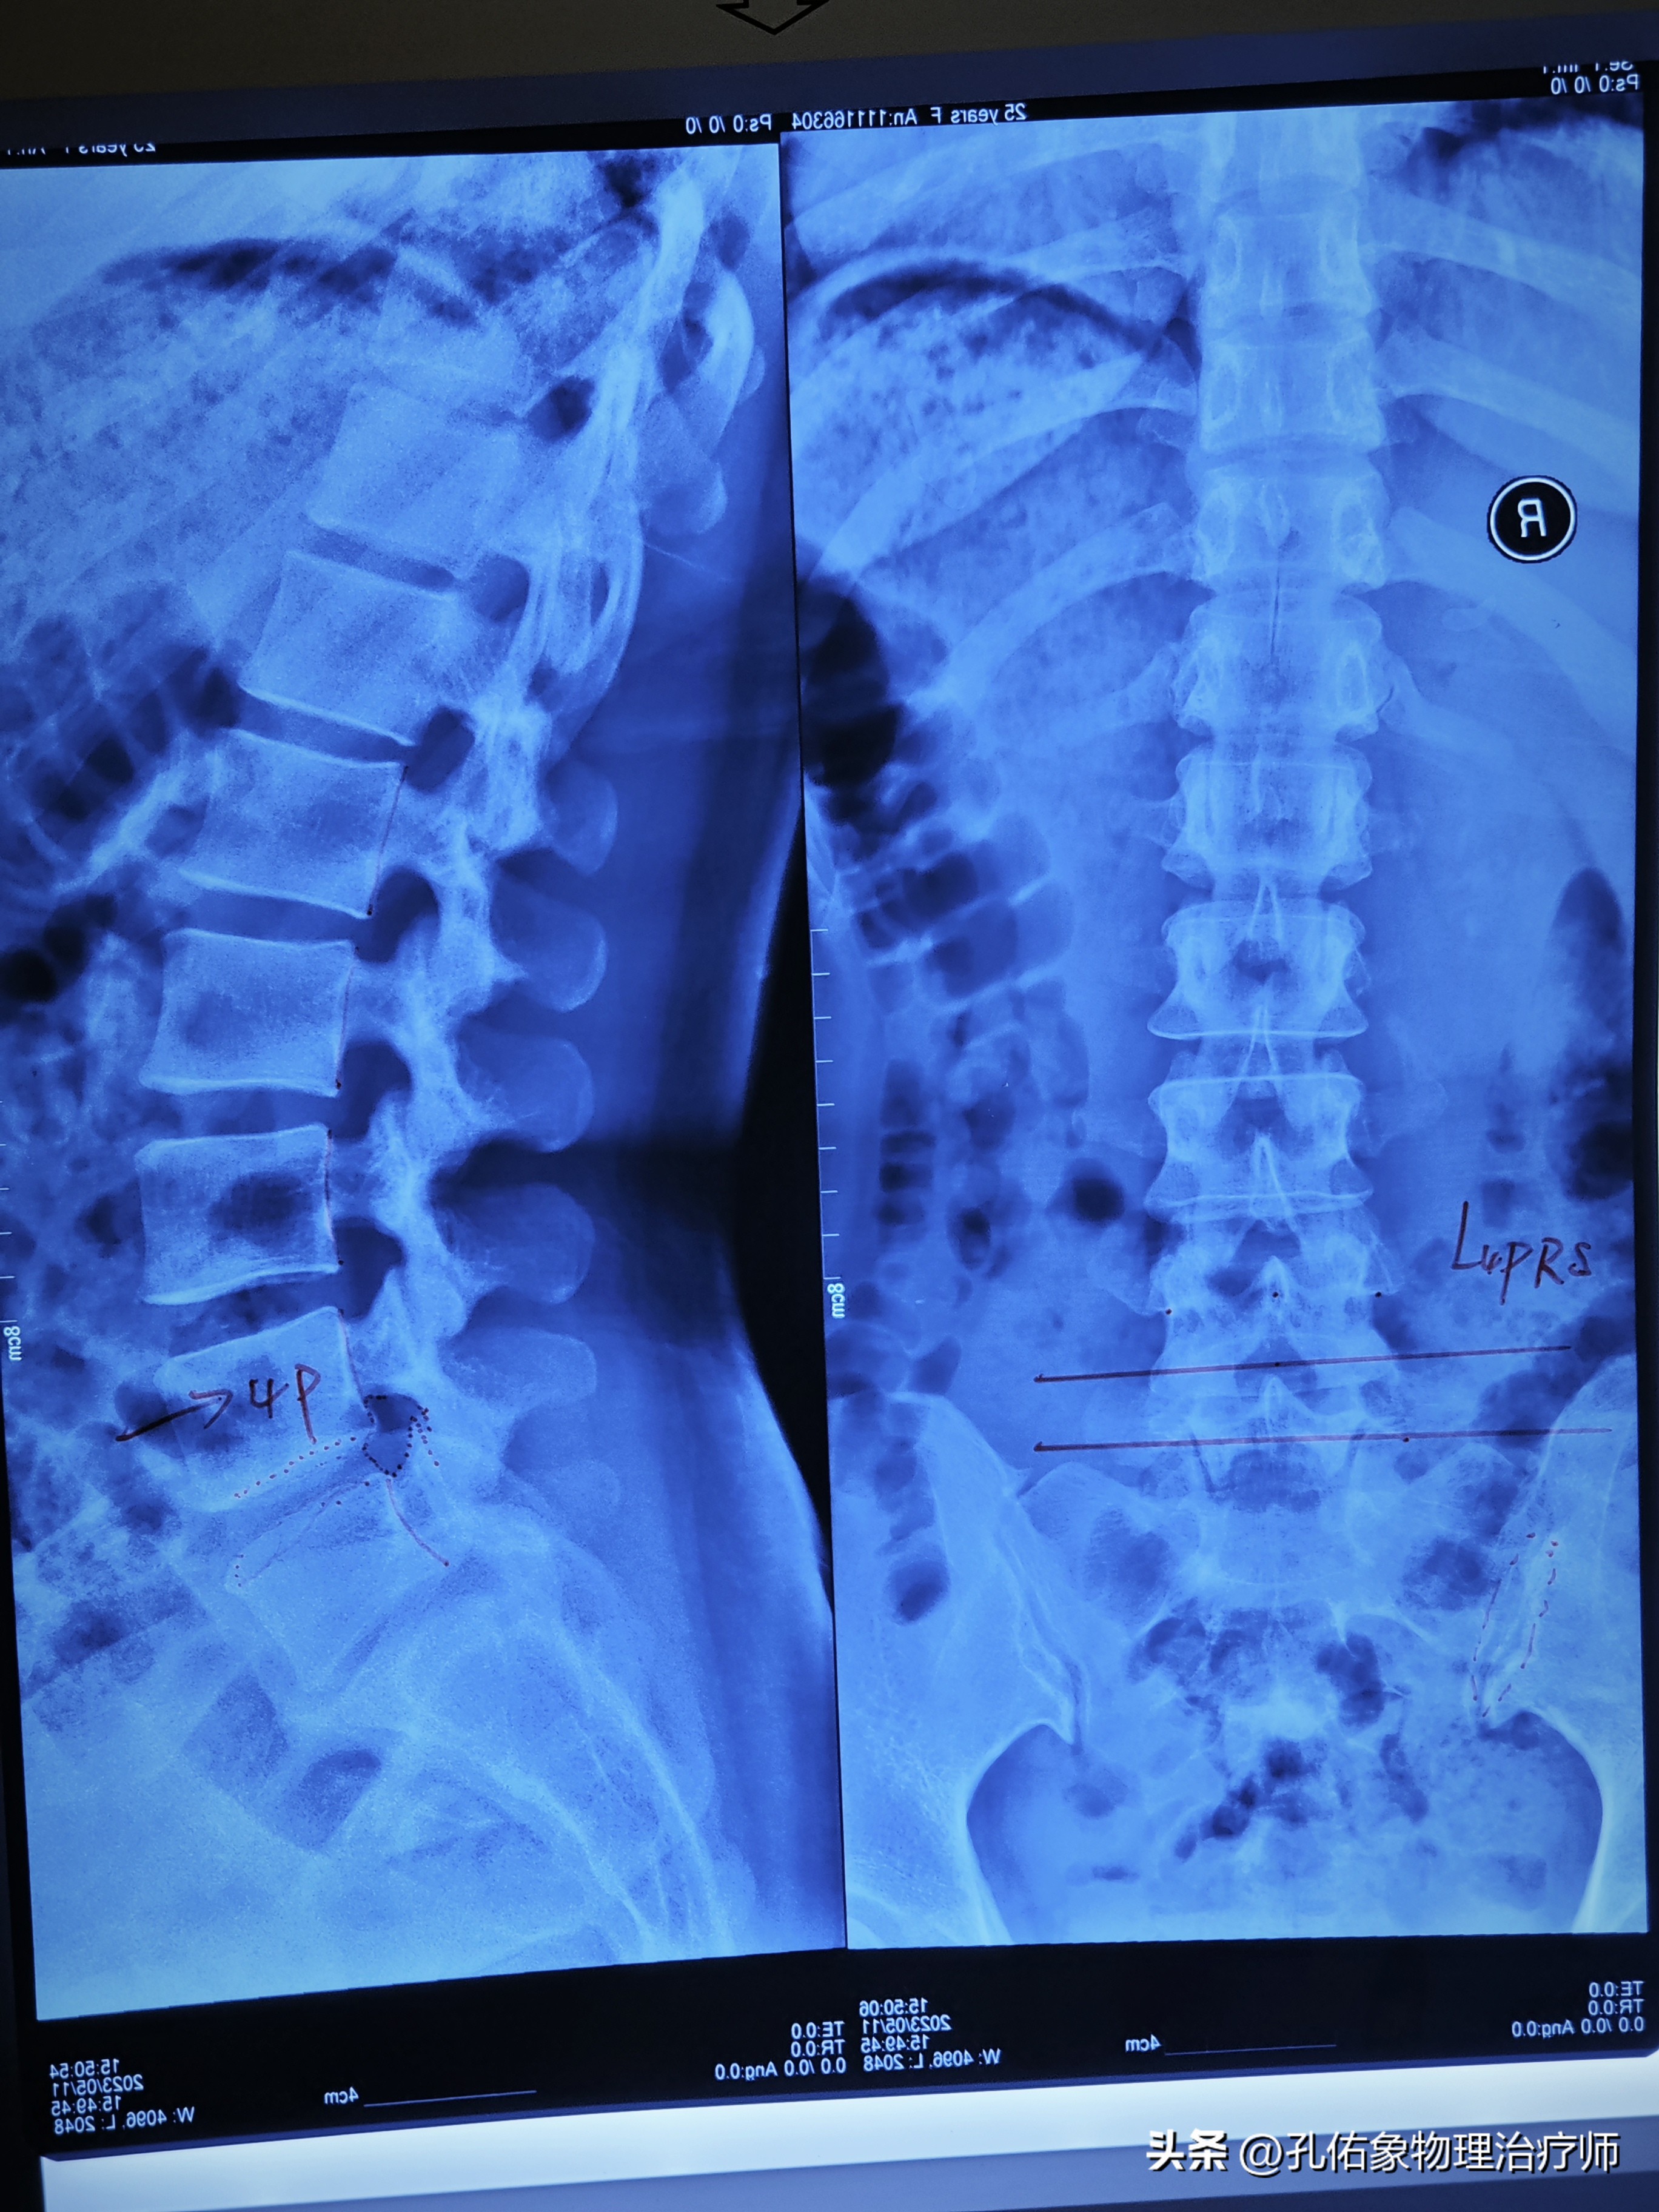

让其拍了一张腰、骨盆X片,结果是下图所示的样子:

阅片提示:腰4椎体相对腰5椎体后下移位,并有旋转;脊柱右侧弯;左右骨盆不等高,右侧骶髂关节钙化。